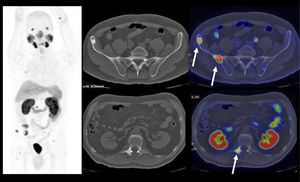

En cáncer vesical con invasión muscular, las metástasis ganglionares y a distancia son de alta frecuencia (Figura 6). En un grupo de 150 pacientes en etapa pT2-4, Shinagare et al (14) describieron un 69% de compromiso secundario ganglionar, 47% óseo, 37% pulmonar, 26% hepático y 16% peritoneal.

Un tema de especial interés es entonces la ocurrencia de metástasis a distancia, ya que pueden cambiar radicalmente el manejo de los pacientes, especialmente la posibilidad de optar o no a cirugía curativa. Ya que las lesiones secundarias óseas son las más frecuentes, es mandatorio optimizar su detección. El PET/CT presenta varias ventajas en esta materia, ya que tiene alta sensibilidad en lesiones líticas, de alta frecuencia en estas neoplasias, y permite evaluar conjuntamente esqueleto axial y apendicular, ya que las metástasis a huesos largos no son poco frecuentes en estas neoplasias (14,20) (Figura 6).